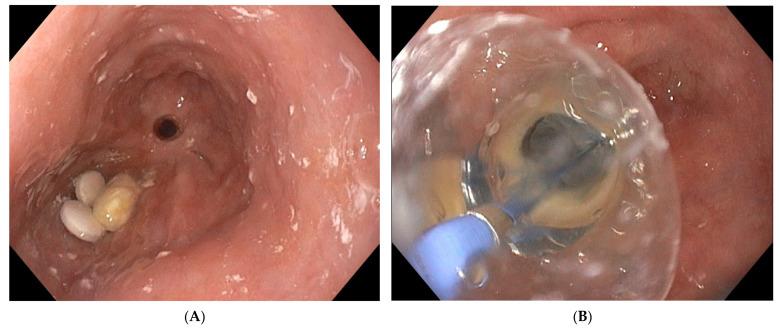

Anastomotic leaks after gastrointestinal surgery have an important impact on surgical outcomes because of the high morbidity and mortality rates. Multiple treatment options exist requiring an individualized patient-tailored treatment plan after multidisciplinary discussion. Endoscopic vacuum therapy (EVT) is a novel treatment option that is nowadays recognized as an effective and useful endoscopic approach to treat leaks or perforations in both the upper and lower gastrointestinal tract. EVT has a very good safety profile. However, it is a time-consuming endeavour requiring engagement from the endoscopist and understanding from the patient. To the unexperienced, the EVT technique may be prone to several hurdles which may deter endoscopists from using it and depriving patients from a potentially life-saving therapeutic option. The current review highlights the possible difficulties of the EVT procedure and aims to provide some practical solutions to facilitate its use in daily clinical practice. Personal tips and tricks are shared to overcome the pre-, intra- and post-procedural hurdles. An instructive video of the procedure helps to illustrate the technique of EVT.

胃肠手术后的吻合口漏由于其高发病率和死亡率,对外科手术结果有重要影响。存在多种治疗选择,需要在多学科讨论后制定个体化的患者定制治疗方案。内镜下真空治疗(EVT)是一种新型治疗选择,如今被认为是治疗上、下消化道漏或穿孔的一种有效且有用的内镜方法。EVT具有非常好的安全性。然而,这是一项耗时的工作,需要内镜医师的参与以及患者的理解。对于没有经验的人来说,EVT技术可能容易遇到几个障碍,这可能会阻碍内镜医师使用它,使患者失去一种可能挽救生命的治疗选择。本综述强调了EVT操作可能存在的困难,旨在提供一些实用的解决方案,以促进其在日常临床实践中的应用。分享了个人的技巧和窍门,以克服术前、术中和术后的障碍。一段该操作的指导性视频有助于说明EVT技术。